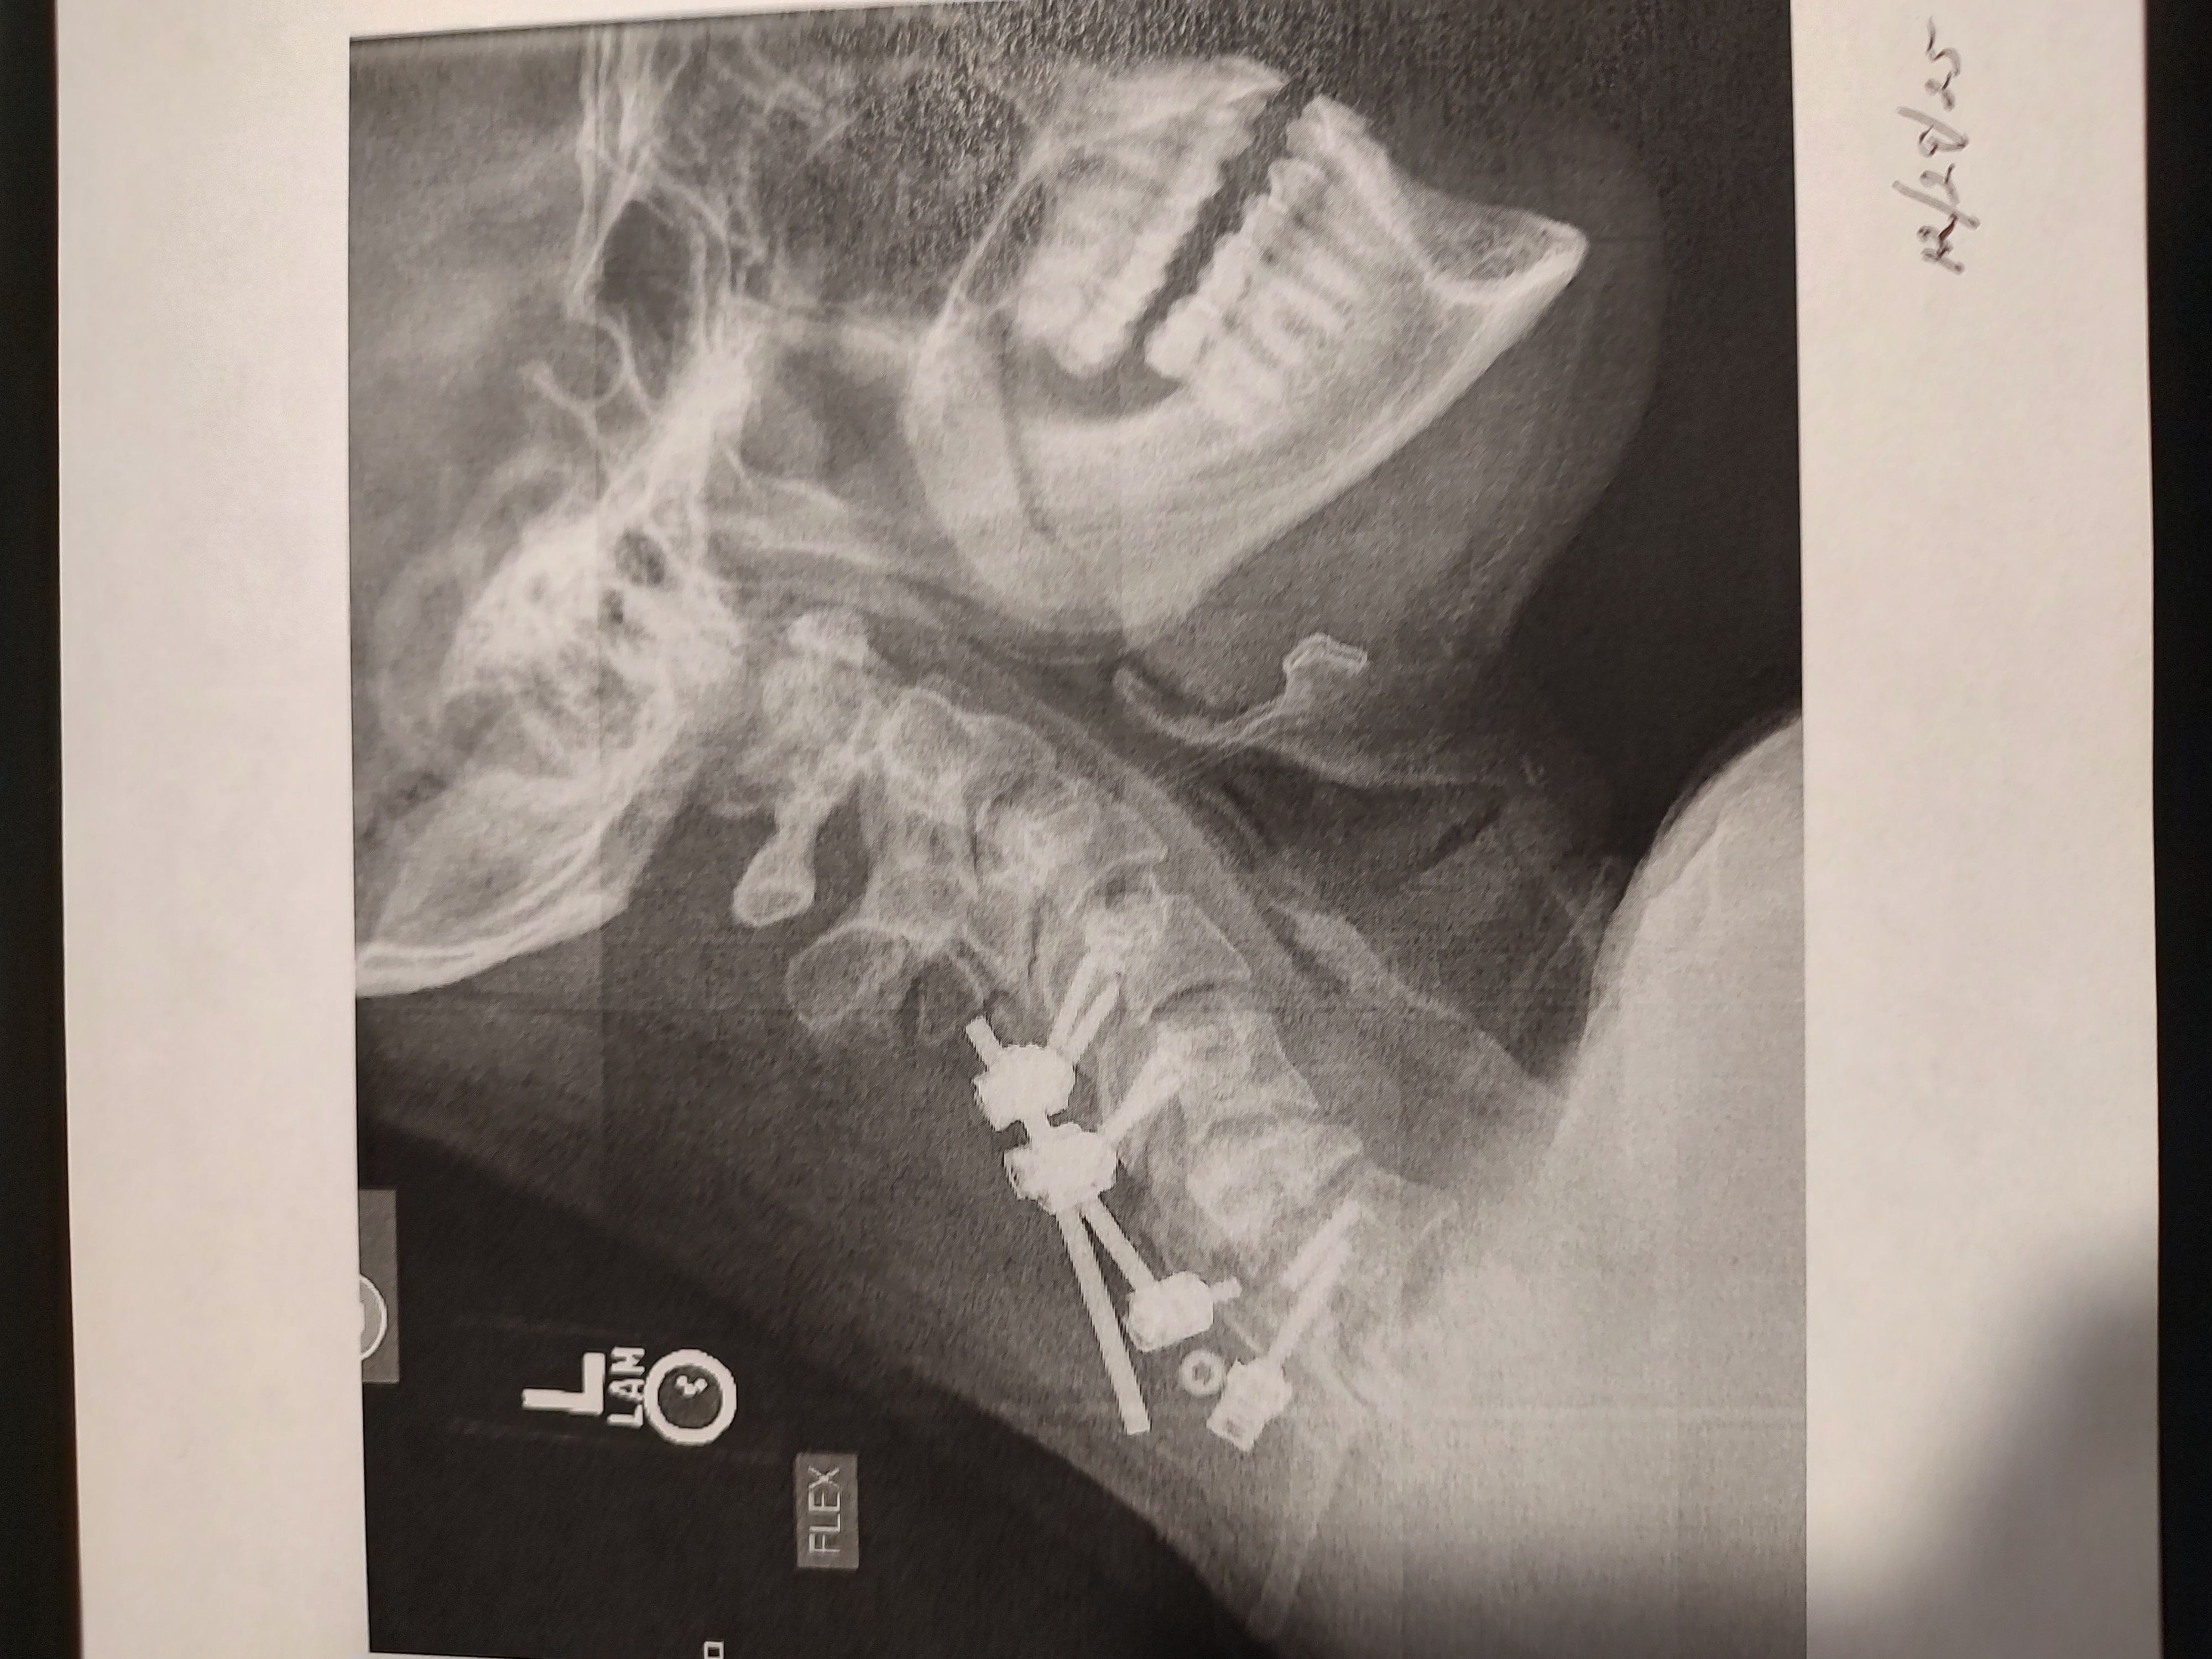

Seth has had surgery for a broken neck back in June 2025. His neck brace broke 3 times not even a month after his surgery, his recent X-ray on December 29th showed that the rod broke off the screw and has a curve starting in his neck, so he has to have surgery again sometime this month. He has not had any income so we are asking for help for his car insurance bill and keeping his phone on and just everyday living expenses food, hygiene products and some minor car repairs.